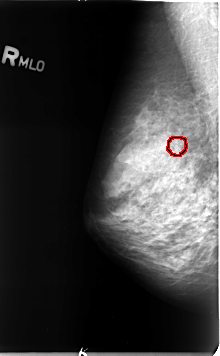

B_3079_1.RIGHT_MLO

RIGHT_MLO LINES 4616 PIXELS_PER_LINE 2856 BITS_PER_PIXEL 12 RESOLUTION 50 OVERLAY

FILE: B_3079_1.RIGHT_MLO.OVERLAY

TOTAL_ABNORMALITIES 1

ABNORMALITY 1

LESION_TYPE CALCIFICATION TYPE PLEOMORPHIC DISTRIBUTION CLUSTERED

ASSESSMENT 4

SUBTLETY 4

PATHOLOGY MALIGNANT

TOTAL_OUTLINES 1

BOUNDARY